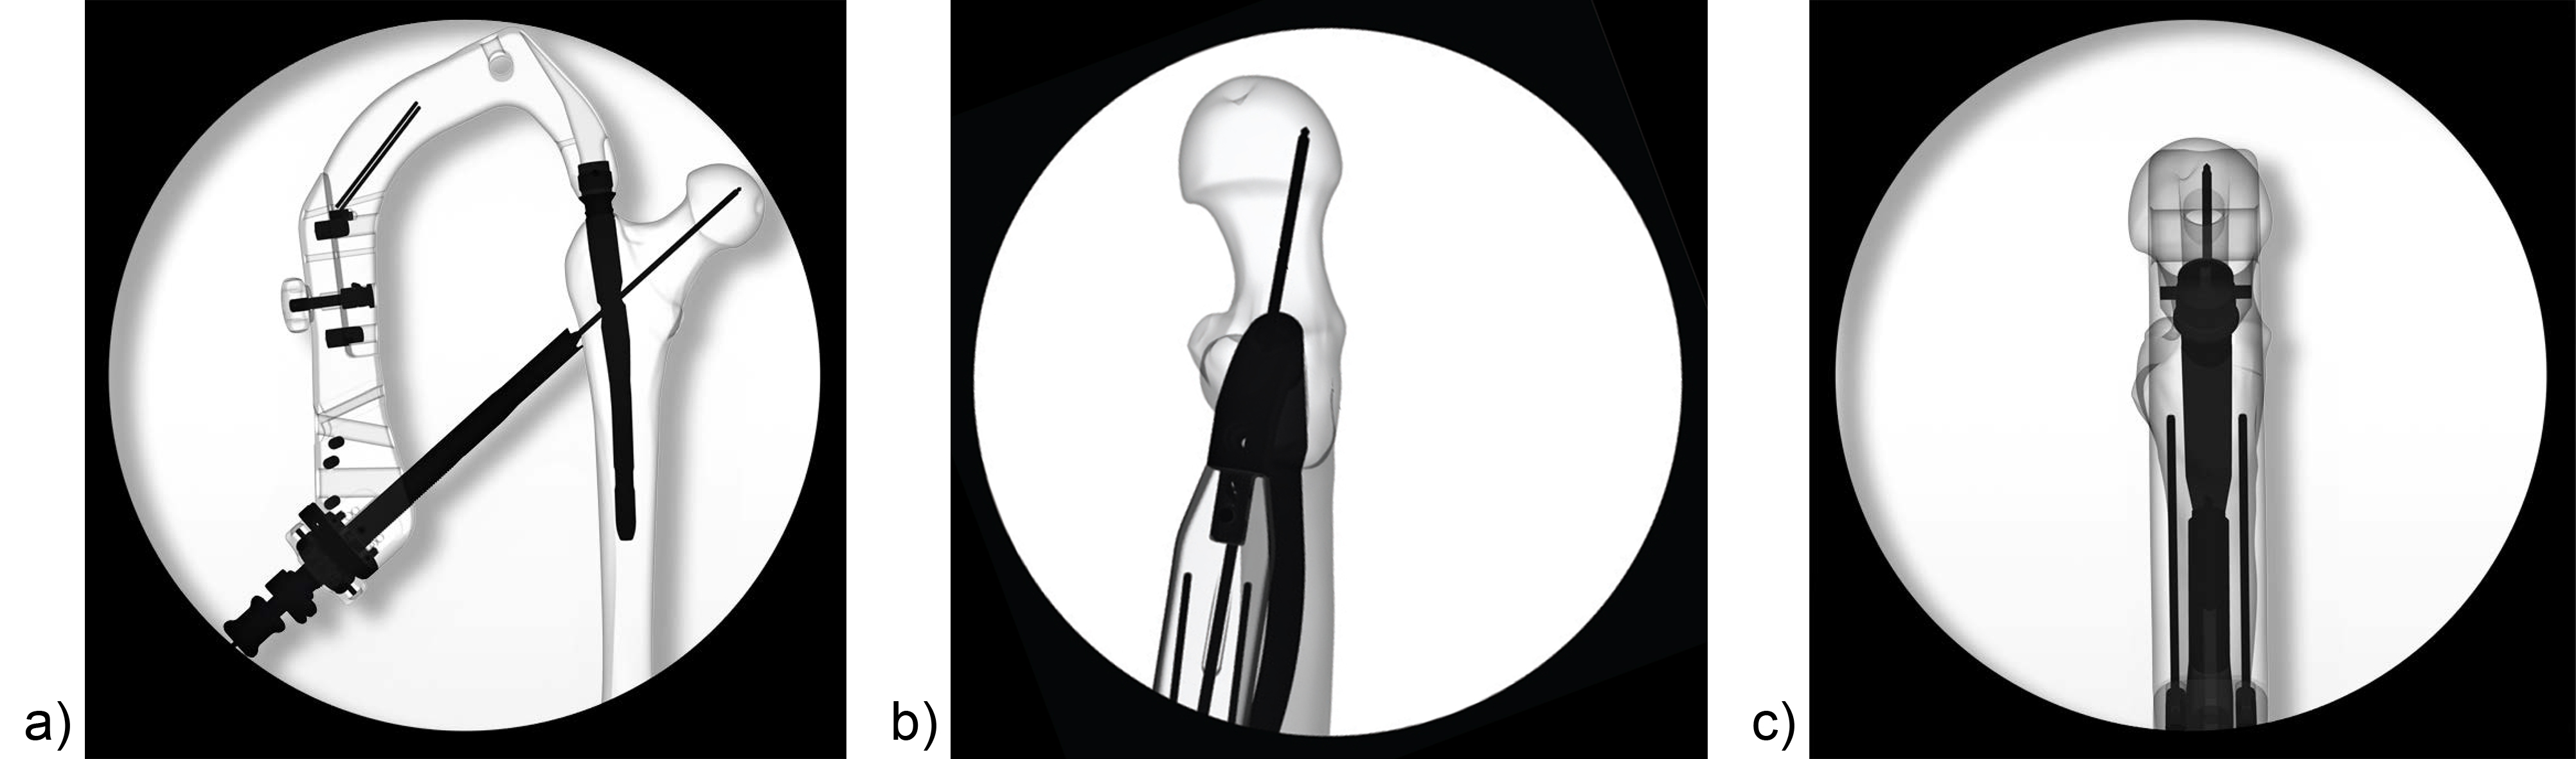

Apart from the newly introduced nail design features, which help to maintain a good reduction, it is also essential to place the head element in the correct position of the femoral head to avoid cut-out or cut-through. Numerous studies have demonstrated that a center/center position of the head element ensures the best clinical outcome. Multiple instrument features, including a multi hole drill sleeve for the facilitation of precise nail entry and aiming aids to accommodate the placement of the head element guide wire in the correct position have been added to the TFNA system to enable accurate implant placement. The insertion handle is radiolucent and has radiographic indicators to help the surgeon with exact guide wire placement for head element positioning in the lateral view (Fig 5). This feature, together with the guide wire aiming device, which checks guide wire position in the AP view, is influential in the placement of the guide wire in the center/center position of the femoral head. It also helps to reduce the number of imaging maneuvers and x-ray shots required.